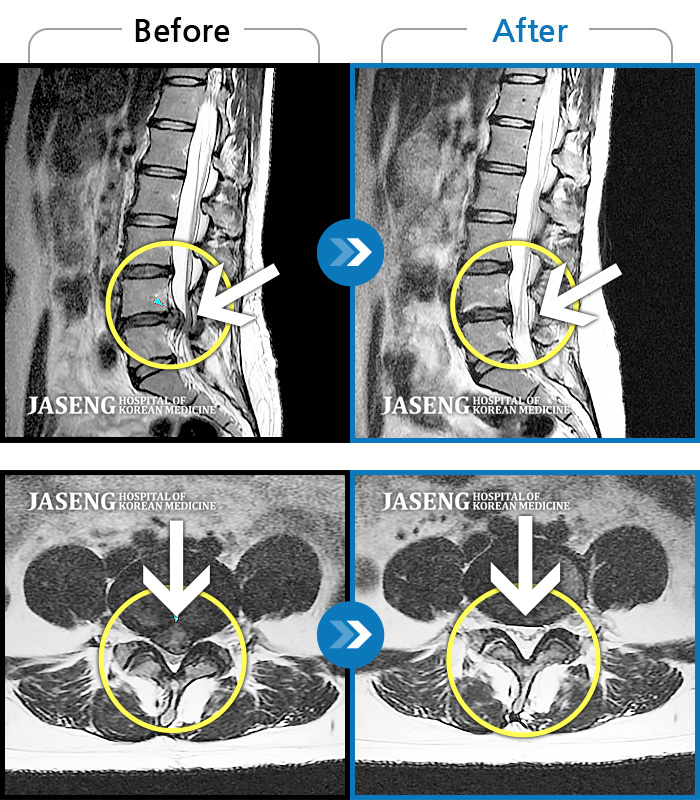

허리디스크

보라매 · 왕오호 원장

허리 통증, 똑바로 서려고 하거나 걸을 때 양쪽 허벅지와 고관절 시큰거림

촬영시기

2017.06.07 ~ 2018.04.17

2018.12.28

조회수 4,138